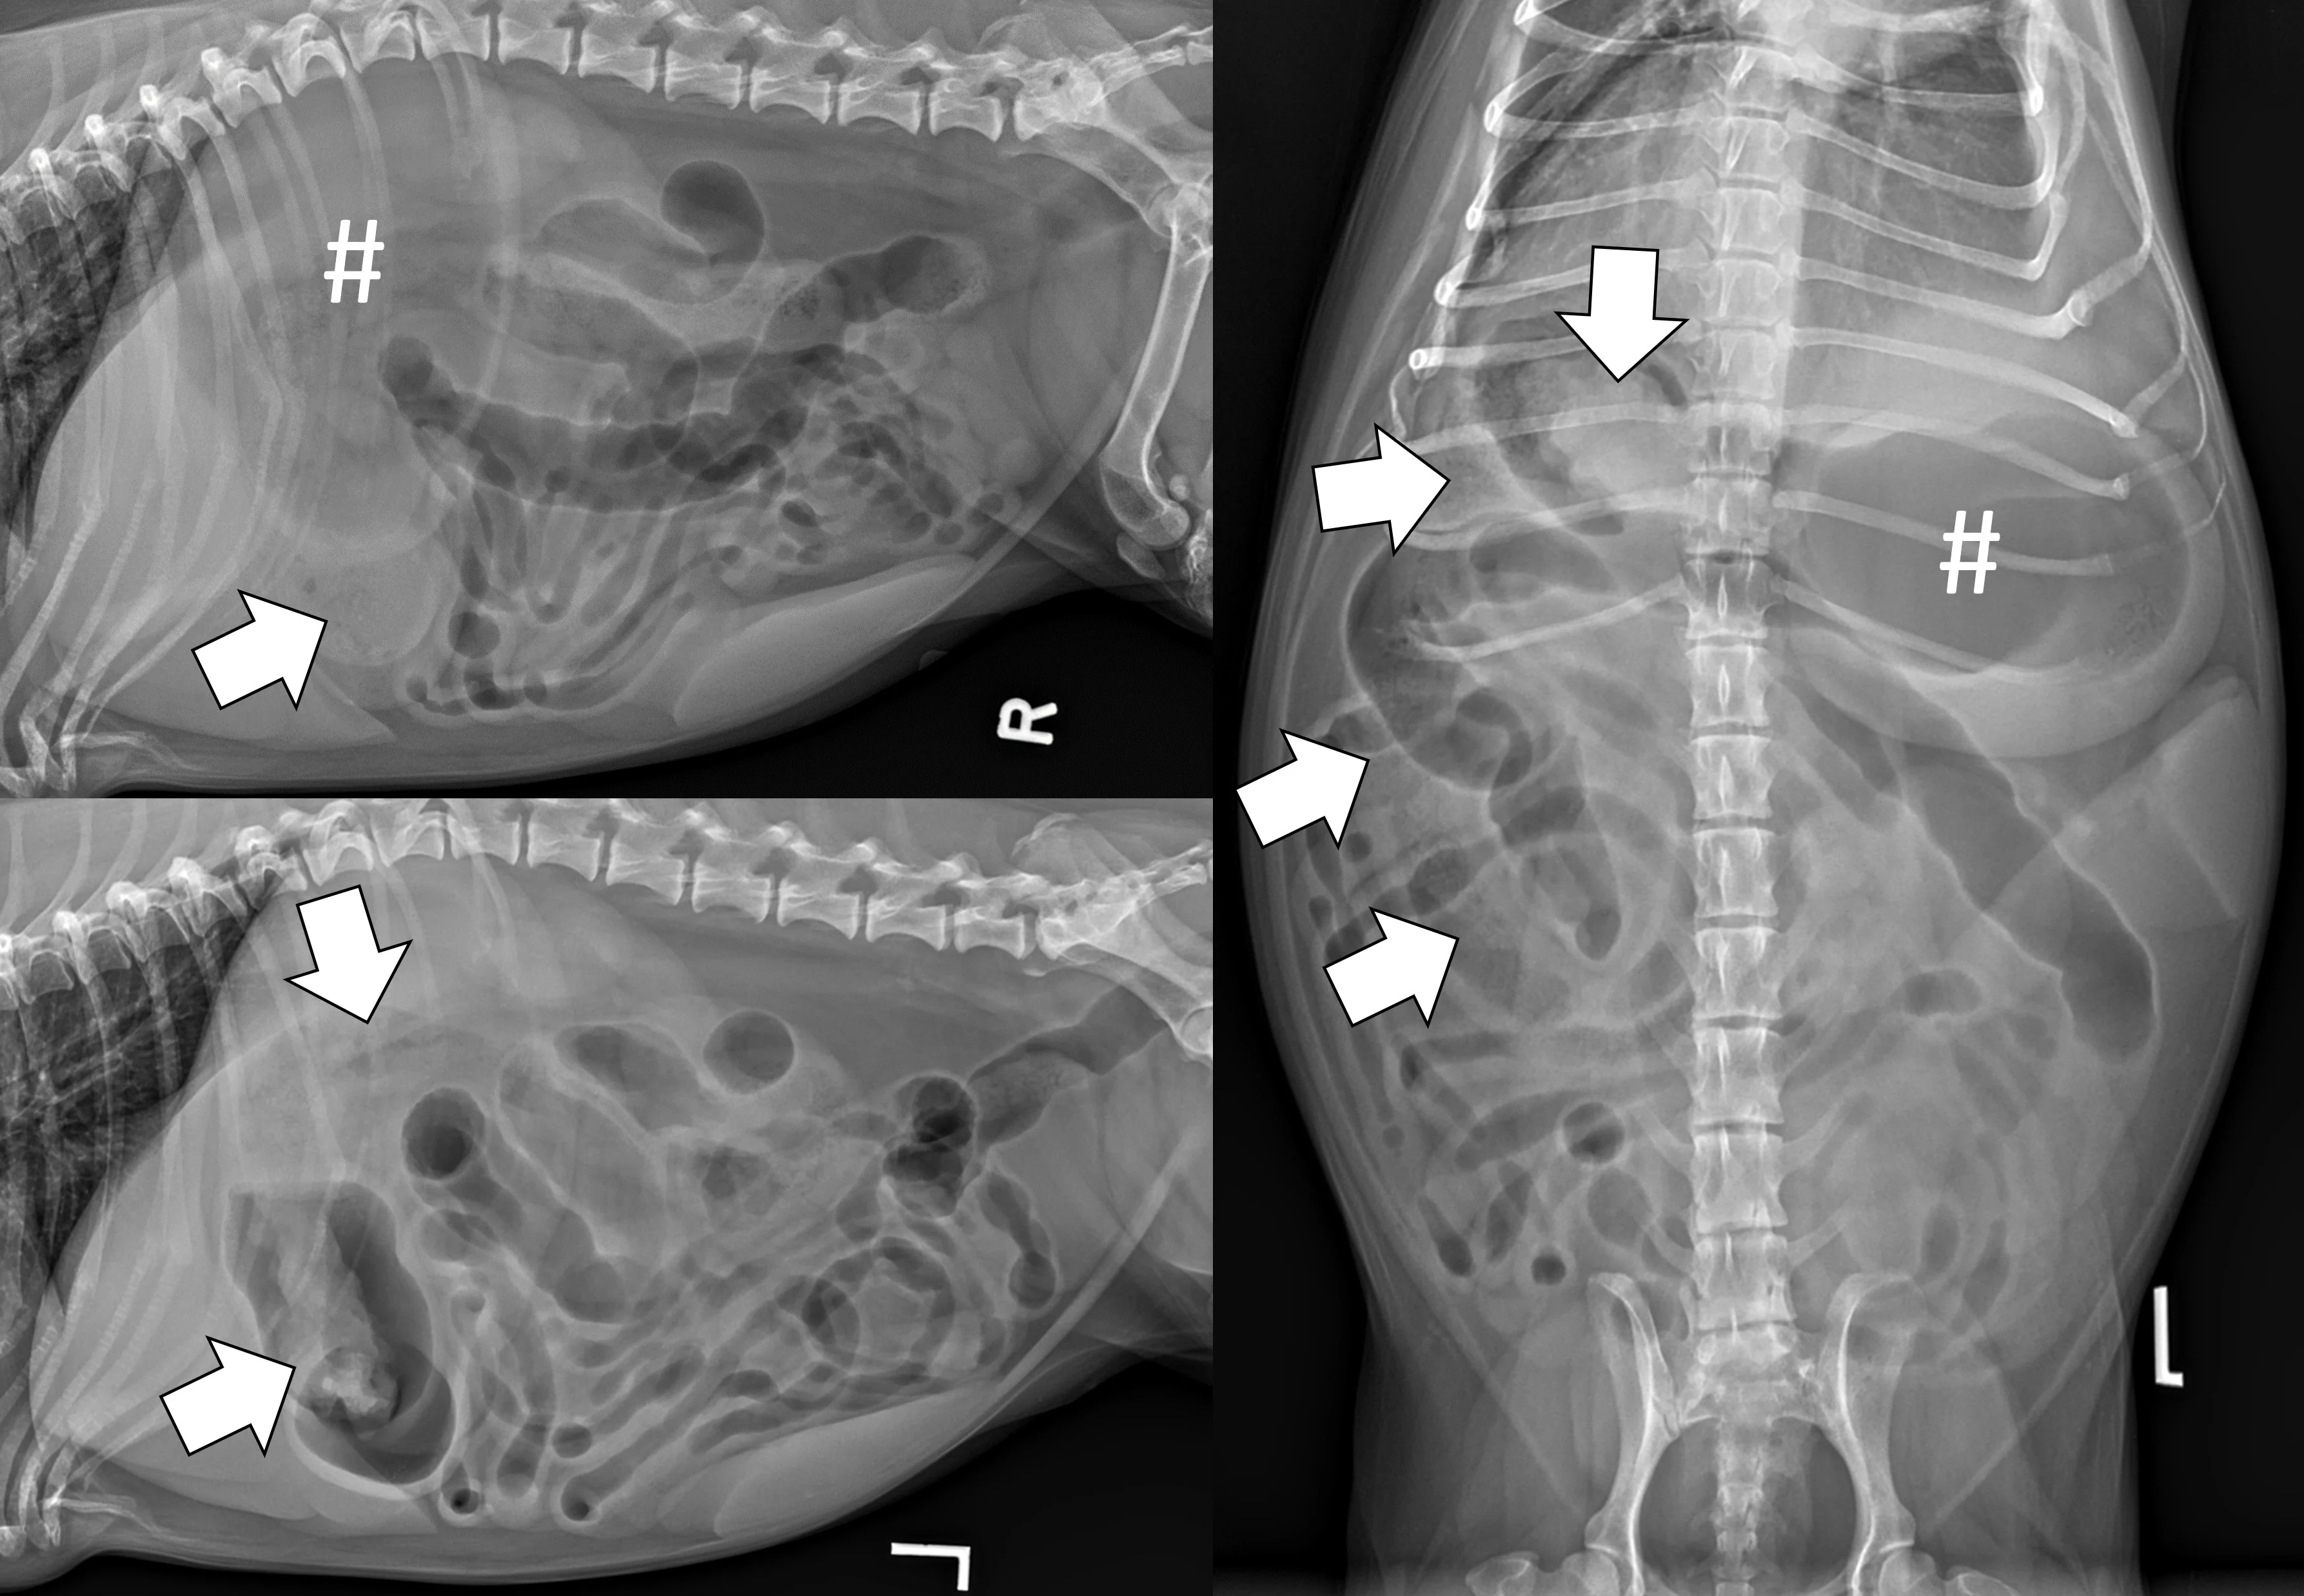

A complete radiographic study includes left lateral, ventrodorsal, and right lateral projections. Obtaining a left lateral projection and performing projections in the aforementioned order can improve visualization of the pylorus and duodenum by shifting gas into the lumens.3 Normal intraluminal gas is an in vivo negative contrast agent that can make soft tissue opaque foreign bodies (eg, cloth) easier to see (Figure 1).

Three-view abdominal radiographs of a 6-year-old spayed dachshund with an acute pyloric outflow obstruction secondary to a surgically confirmed foreign body (cloth). The stomach (pound signs) is moderately dilated with gas and fluid. On the left lateral and ventrodorsal projections, gas outlines an irregularly shaped soft tissue opaque foreign body (arrows) within the pylorus that extends into the duodenum. On the right lateral projection, the foreign body is more difficult to see because it is surrounded by similarly opaque gastric fluid.